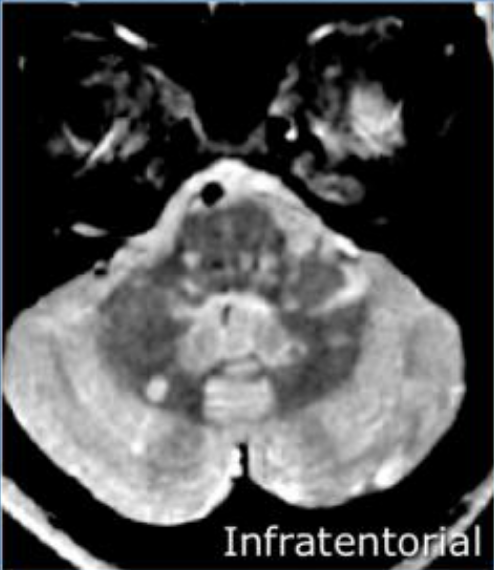

Exames de Imagem

incluir as imagens e as caracteristicas de em